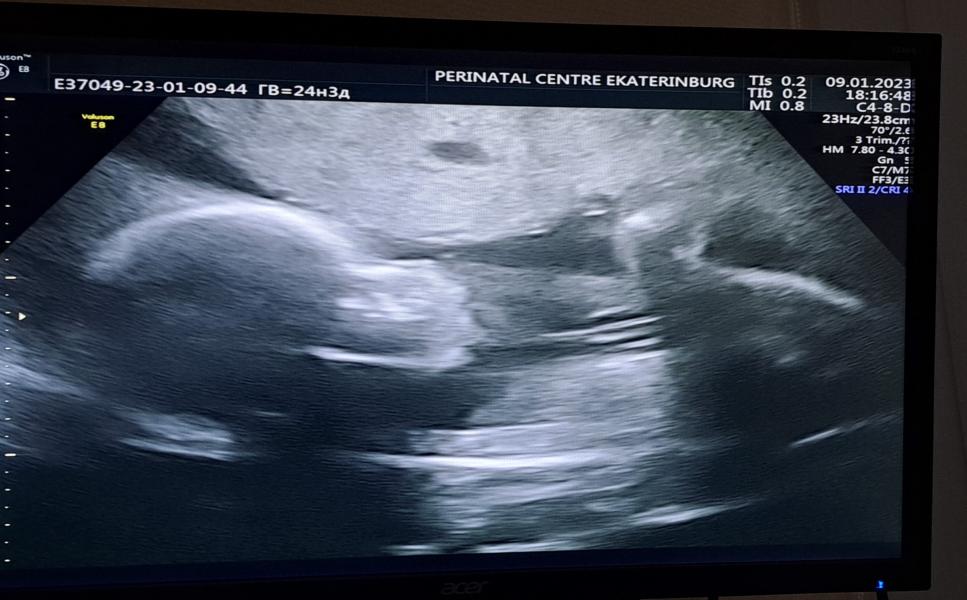

Сегодня ходила на прием, перед ним тут же краткое узи, для измерения размеров.

Итого у моего ляли все отлично, сидит на попе, смотрит мне в бок, весит 770 гр, с кровотокам все отлично :)